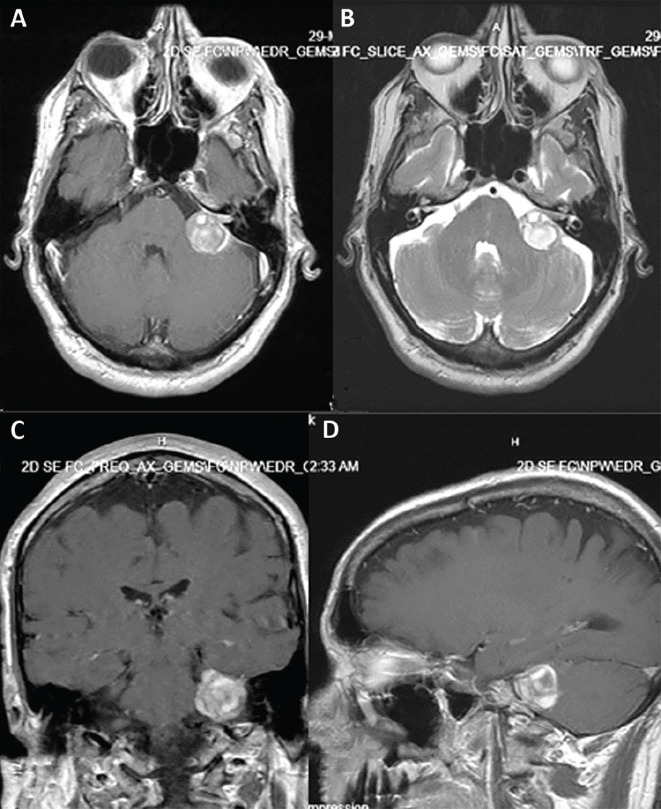

Objective: Anticoagulant therapy is a risk factor for repeated intratumoral hemorrhage and acute enlargement of a vestibular schwannoma (VS) with neurological deficits. Therefore, we describe two cases of patients on oral anticoagulant therapy with intratumoral hemorrhage in which anticoagulant therapy prior to surgical resection was discontinued. We also discuss other similar cases from the literature since this is a rare event.

Case reports: We described the two cases of intratumoral hemorrhage in acoustic neurinoma and conducted a literature review of similar cases of patients with intratumoral hemorrhage in acoustic neurinoma who were also on oral anticoagulants. Both patients presented with CN-VII palsy prior to surgery; both also fully re-covered after surgery except for hearing loss on the tumor side. Our literature review found 50 cases of VS (reported as vestibular schwannomas in the literature) with intratumoral hemorrhage. From this total, 11 patients used oral anticoagulant therapy with reported poor outcomes and high mortality; 9 of these 11 cases were reported in the past 20 years. The incidence is expected to rise due to increased use of anticoagulant therapy due to onset of atrial fibrillation, atherosclerosis, and thromboembolism from longer human lifespan.

Conclusion: Anticoagulant therapy represents a risk factor for intratumoral hemorrhage and acute enlargement of VS tumor mass with neurological deficits.